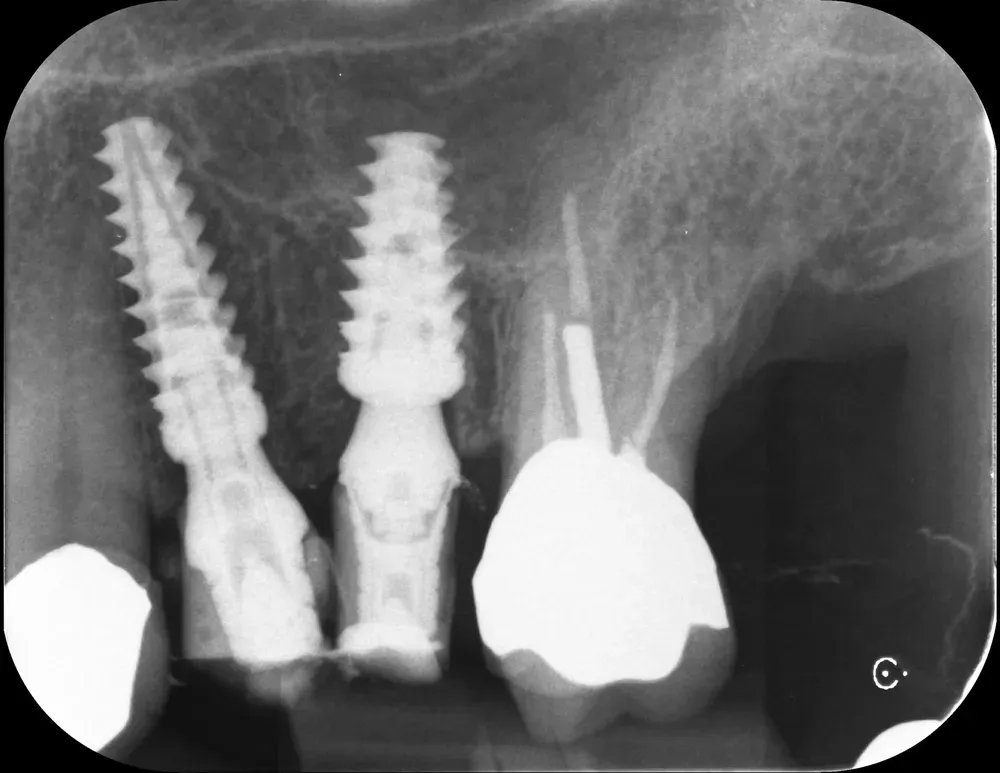

Con gli espansori da 13mm in posizione ho effettuato un controllo radiografico della posizione, prima di procedere ulteriormente.

Strumenti espansori da 13mm in posizione